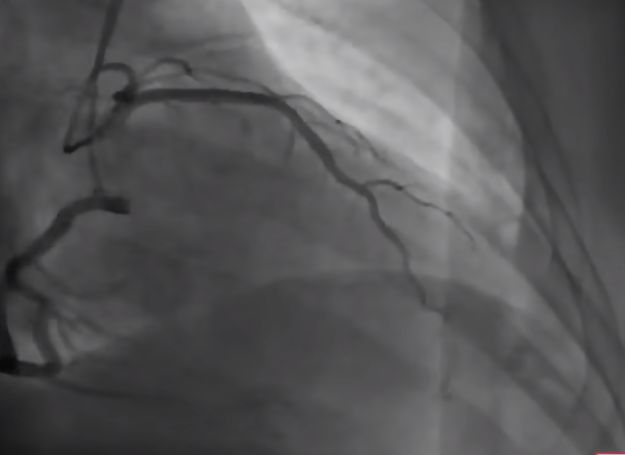

마지막 확진방법이, 필요하면 관상동맥조영술1

- 시술이다. 실시간으로 엑스레이 영상을 찍어보면서 의심가는 관상동맥입구(여기까지는 다리 혈관을 찔러 가는 관을 심장까지 보낸다)에서 조영제를 흘리면, 관상동맥이 막힌 데까지만 조영제가 흘러들어가는 게 엑스레이로 보인다. [본문으로]